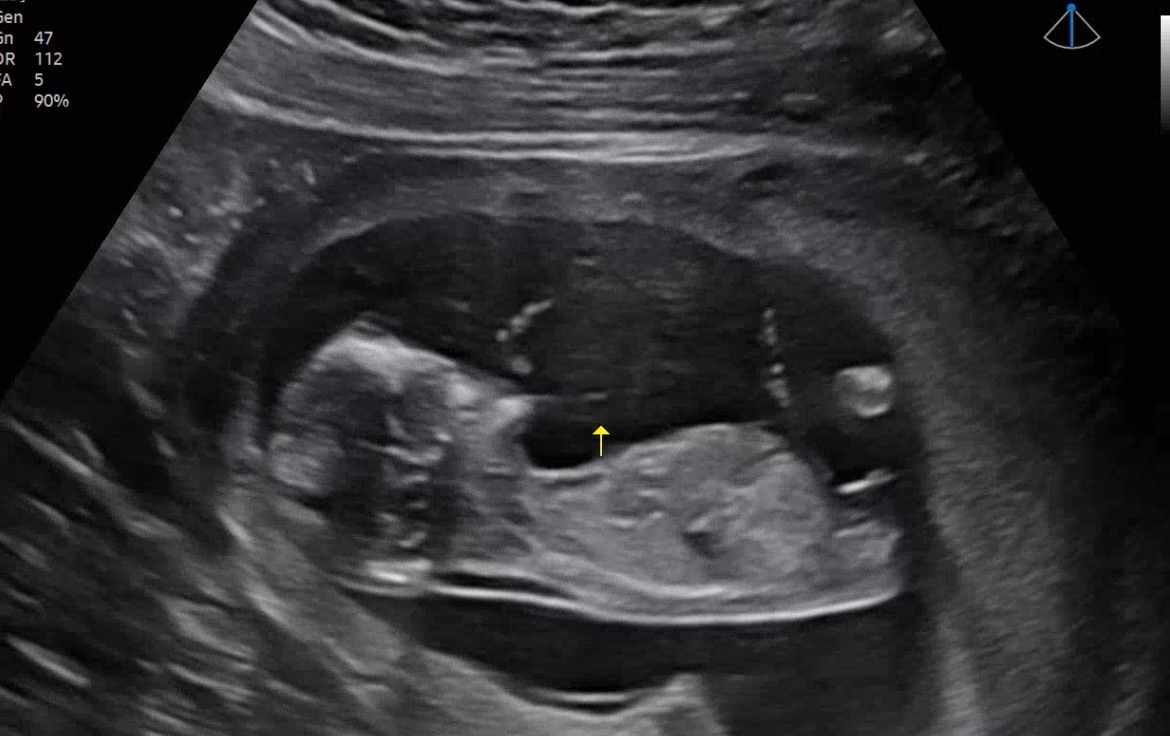

12주 3일 각도법 궁금해요 !

고수님들 아들일까요 딸일까요!